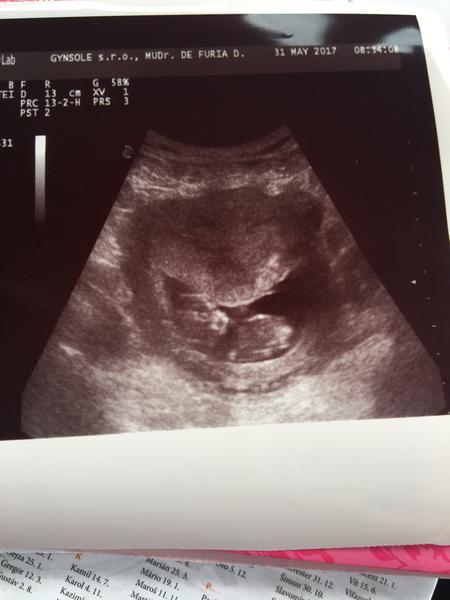

@kudusko, a vsetky ostatne kocky, chcela by som sa vam pochvalit mojim malym piskotom 😇 foto sona je sice dva tyzdne stare ale nevadi 🤗 stihli sme aj tehu fotenie, no v tom teple to uz nebola ziadna slava sa valat po zemi 😅 ale tak co clovek neurobi pre krasnu spomienku 😎 zeny, zelam vam krasny slnecny den, my sa uz doma schovavame 😁

@bluebell0412 @luta13 @miriamn76 @happymia a ostatne babulky tak tu je môj nezbednik/ca 😍 Všetko je Ok tak sa šantilo v brušku že dr nevedela odmerať tak mame 4,5 alebo 4,7cm cca srdiečko krásne bilo podľa ms sme 10+5 podľa miminká 11+2 zajtra ideme na 3D veľmi som šťastná a prajem to šťastie každej žene 😘

@barborapavlikova ďakujem mojko aj Vám želám len a len zdravicko veru veľmi rýchlo rastu akurát som si pozrela foto z troch kontrol a že Waw..no dr vravela že 4tehulky predomnou sa poslala poprechádzať lebo spinkali a moje bolo akčné pretacalo sa 😃 Ale videla som rúčky nôžky všetko Ok zajtra bude krajšia foto len dúfam že má neobjednali skoro že sa bude dať pozrieť pomerat od 4,5cm je vraj norma na 3D a meranie bábätka